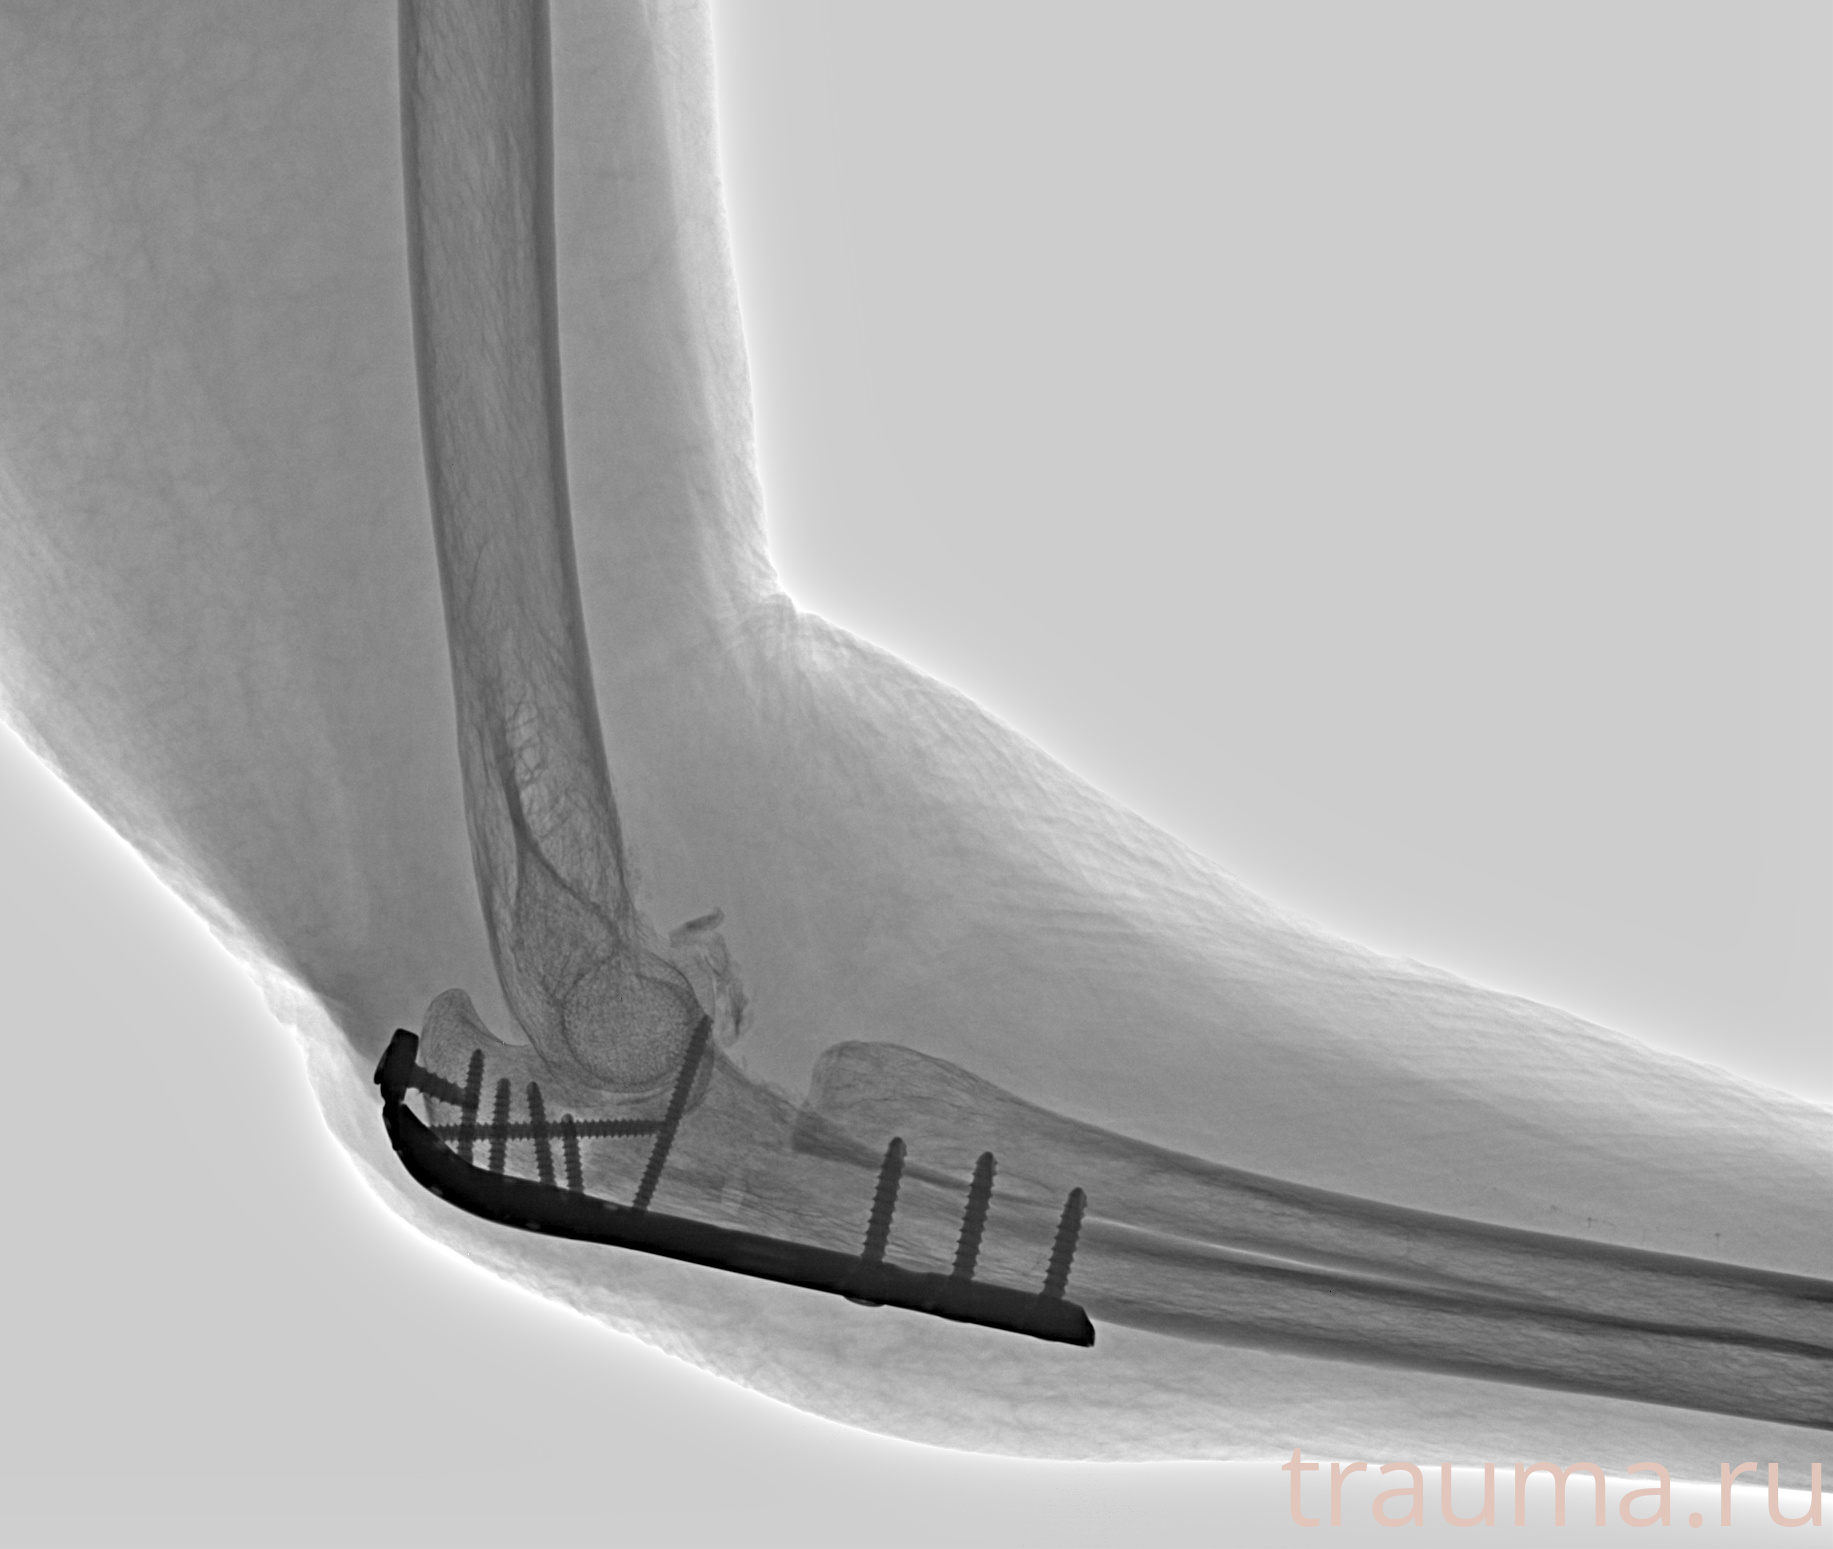

Рентгенограммы